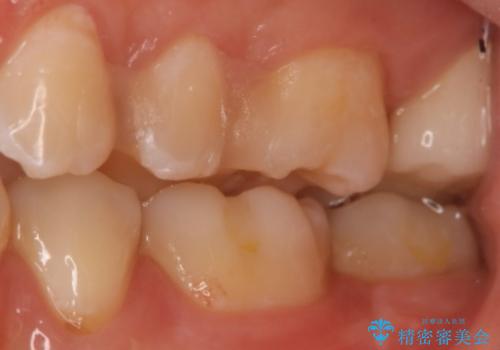

- 左上7番の虫歯治療を主訴に来院された患者様です。

虫歯の範囲が広かったので切削量・形態を考慮し、セラミッククラウンでの治療を計画しました。